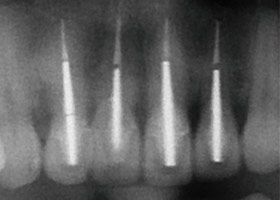

治療後,X光片。